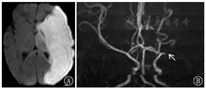

3.2 胆红素脑病对于疑有胆红素脑病的婴儿,在急性期,苍白球内T1WI信号强度的增加明显,T2WI增加较T1WI不明显(图6)[7]或不增加。到6个月后,在T2WI上异常信号变得更加明显,T1WI上信号强度降低。胆红素脑病经典的头颅MRI后期表现:T2WI在苍白球区显示高信号强度(图7)[8],还可累及到丘脑底核和海马等。

图6

胆红素脑病急性期 A:T1加权像:苍白球内信号强度增加明显(箭头所示);B:T2加权像:信号强度增加不明显(箭头所示)

Figure 6

Nuclear jaundice A:T1 weighted image showing subtle but clear increased T1 signal intensity in the globus pallidum bilaterally (arrow showed);B:T2 weighted image showing unremarkable T2 signal intensity in the globus pallidum bilaterally(arrow showed)

点击查看大图

胆红素脑病后期T2加权像:苍白球区显示高信号强度(箭头所示)

Figure 7

Late bilirubin encephalopathy T2 weighted image magnetic resonance image showing bilateral T2 hyperintensities of the globus pallidus(arrow showed)